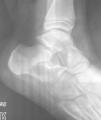

Se presenta el caso de un varón de 9 años que acude a urgencias por dolor en pie derecho de aparición aguda. Radiológicamente existe una lesión osteolítica en calcáneo, que ocupa la mitad del cuerpo, con características de benignidad (fig. 1). El TC muestra una imagen compatible con QOS. Debido al tamaño de la lesión y al riesgo de colapso, se indica el tratamiento quirúrgico: se realiza una ventana en la cortical externa del calcáneo, se curetean las paredes de la cavidad, se perforan las paredes del quiste, y se rellena la cavidad con injerto óseo heterólogo liofilizado (Prosteon®). La anatomía patológica confirma el diagnóstico de QOS. El paciente inicia carga parcial a las 4 semanas de la operación y a los 3 meses inicia actividad deportiva sin dolor. A los 2 años de evolución, radiológicamente se observa la desaparición de la pared esclerosa del quiste, con reabsorción parcial del injerto aportado que es sustituido por hueso trabecular (fig. 2) dando por curada la lesión.